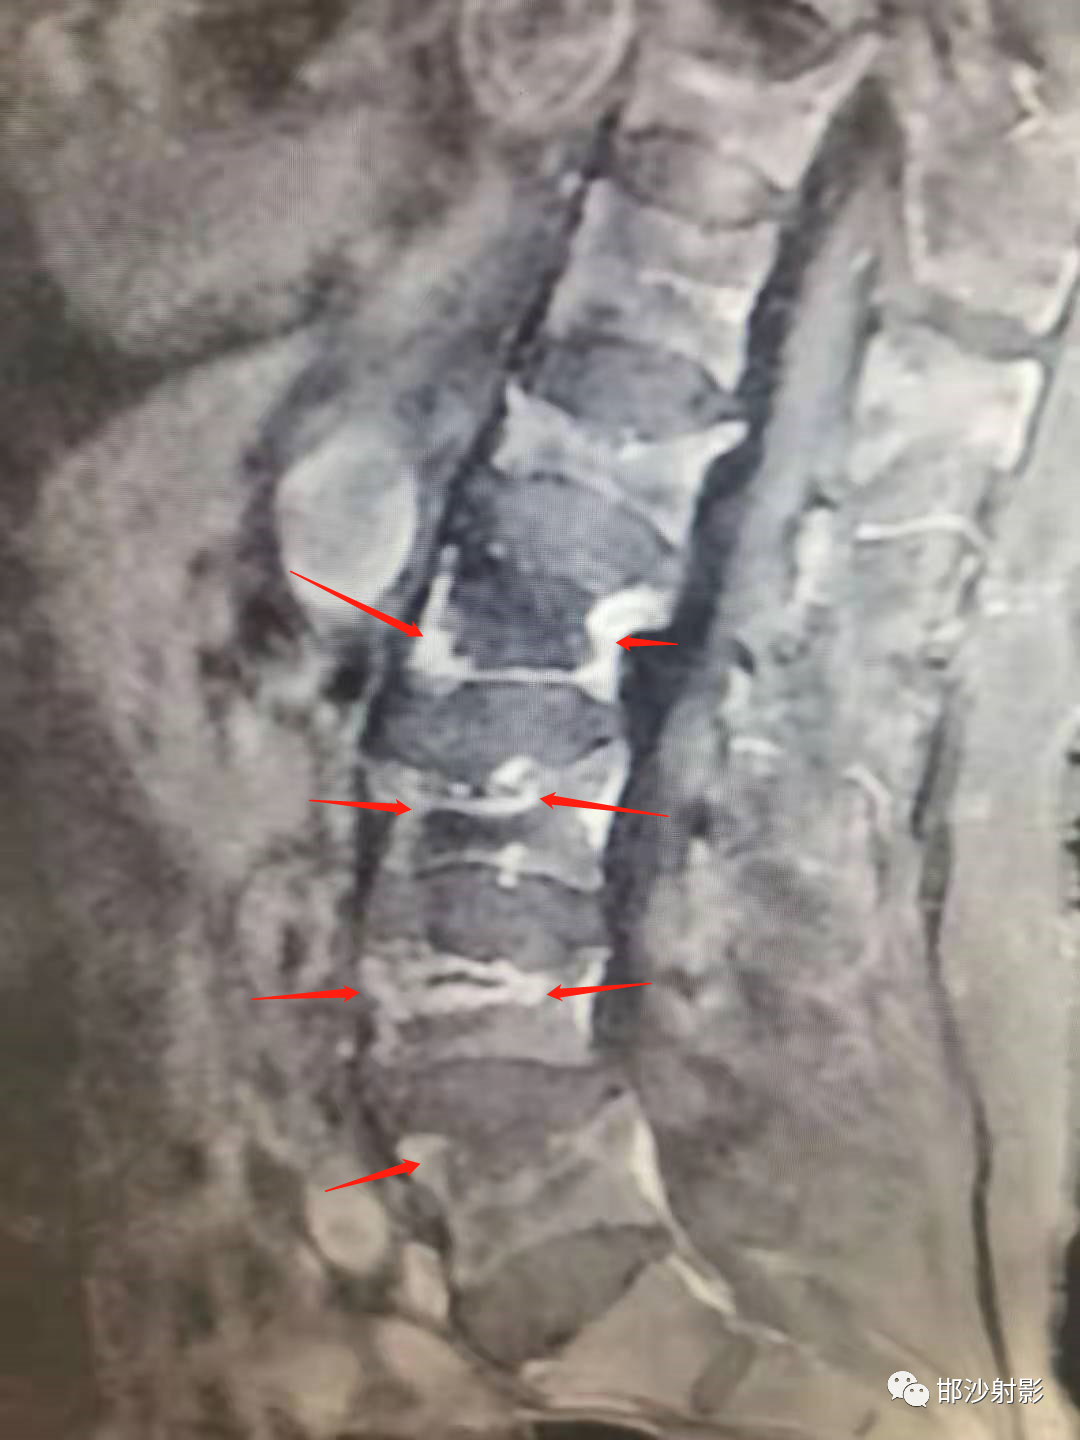

腰椎MRI  T1图像:

T2WI:

T1WI增强扫描:

红箭显示环形肉芽组织强化,呈蛋壳样分布;

MRI:可以有效评估。根据研究发现,MRI 及病理可将 IVC 表现分四型:①液体型,T1WI 低信号、T2WI 散在高信号, 病理学上为广泛的椎体坏死及坏 死后骨吸收;②压缩型,椎体明显楔形变(前柱明显变扁而后 柱无明显变化),T1WI 低信号,T2WI 中等信号,病理上为椎体 坏死、骨髓纤维化、肉芽及反应性新生骨形成;③肉芽组织 型,T1WI 低信号、T2WI 中等信号, 信号分布较压缩型更广且 椎体后部受累及, 病理学为广泛肉芽组织形成;④混合型, MRI 及病理学为前述各型的混合表现。

真空裂隙征(IVC):是椎体缺血坏死的典型表现,前部较后部多见;IVC为渗液时,T1低信号,T2高信号,此征象称为液体征象,高度提示椎体缺血坏死,并可用于鉴别kummell与骨质疏松引起的压缩性骨折,IVC为气体时,MRI均为低信号。

T2WI,双线征(线样高信号被低信号包绕)